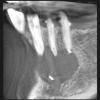

Prosthodontist Опубликовано 2 июля, 2012 Поделиться Опубликовано 2 июля, 2012 Реально ли вылечить эндодонтически? Как вы думаете?http://images.vfl.ru/ii/1341213163/c2792512/687110_m.jpgСейчас канал промыт, старье убрано, лежит каласепт с одной гуттой. Ссылка на комментарий

Prosthodontist Опубликовано 2 июля, 2012 Автор Поделиться Опубликовано 2 июля, 2012 Гутта? Просто не было времени сдедать рентген контроль длинны отдельно с гуттой, решил сделать так, потому что апекс локатор вводил в смуту. Ссылка на комментарий

samsonov Опубликовано 2 июля, 2012 Поделиться Опубликовано 2 июля, 2012 Гутта? Просто не было времени сдедать рентген контроль длинны отдельно с гуттой, решил сделать так, потому что апекс локатор вводил в смуту.апекслокатор может обманывать из-за жидкости в канале и деструкции верхушки,каласепт,имхо,мешает чётче увидеть структуру... Ссылка на комментарий